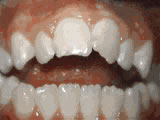

Open bite - Front teeth don't touch

open bite beforeBefore

open bite afterAfter

Patient sucked her thumb as a young child. She started treatment at age 13. She had braces and a special appliance — called a crib — to retrain the tongue, for 28 months. Now she can bite the lettuce out of a sandwich.